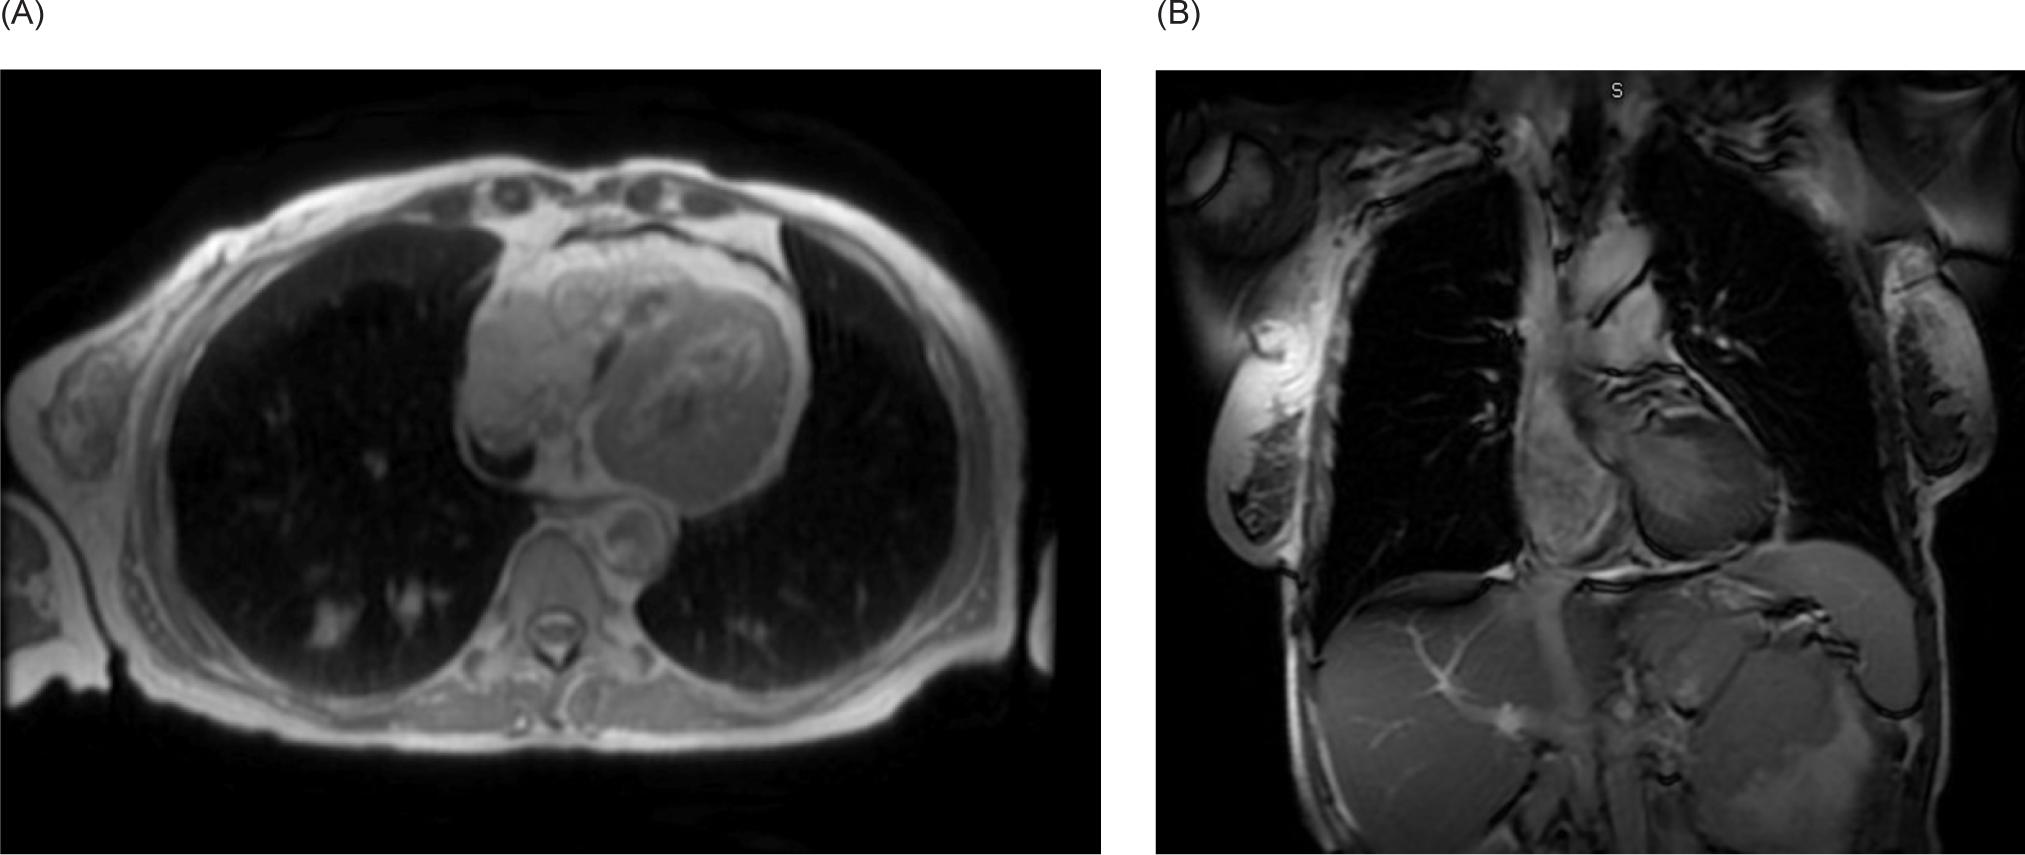

A 59-year-old female smoker with history of hypertension and hyperlipidemia who was screened for lung cancer with yearly low-dose CT scans was incidentally found to have a large left renal mass. Further evaluation via CT revealed a complex enhancing renal mass measuring 9.2.2 × 9.3 × 12.4 cm with extension into the left psoas muscle and abutting the pancreatic tail, spleen, and stomach (Figure 1). The patient underwent excision of a soft tissue mass, and surgical pathology was consistent with sarcoma. PET-CT scan revealed multiple avid lesions including lung nodules of up to 1.5 cm, a left adrenal mass, retroperitoneal adenopathy, and soft tissue metastases in the pelvic muscles as well as a lesion near the right atrium (Figure 2). An echocardiogram was performed in order to further evaluate the cardiac finding on the PET-CT scan, which revealed a 3.5 × 3.4 cm mass attached to the right atrial free wall, which was thought to represent a large thrombus or cardiac tumor, as well as a 0.75 cm mass noted on the atrial aspect of the IVC-RA junction likely representing the thrombus. Left ventricle ejection fraction was normal at 65%. The patient was instructed by her cardiologist to present to the Emergency Department for further evaluation given these findings. On presentation, the patient reported intermittent left flank pain, EKG was normal sinus rhythm with no acute ST changes, and CTA scan revealed likely invasion of perivascular nodules in the right upper lobe into subsegmental pulmonary arterial branches with associated pulmonary emboli within the distal subsegmental and more distal branches. The following day, cardiac MRI confirmed an intra-cardiac tumor occupying the entire right atrium with extension through the myocardium into the epicardial space and through the tricuspid valve into the right ventricle (Figure 3). MRI brain revealed three lesions consistent with metastatic disease. Renal biopsy was consistent with clear cell RCC with sarcomatoid features (Figure 4). Immunohistochemical studies were positive for desmin, PAX8, and myogenin, and negative for CK7. Patient was identified as poor risk per International Metastatic RCC Database Consortium (IMDC), with a median survival of 7.8 months. The patient received Ipilimumab and Nivolumab for one cycle, followed by Nivolumab only due to complication of diarrhea requiring steroid therapy. After three months of therapy that included three cycles of total therapy, she was noted to have partial response per Response Evaluation Criteria in Solid Tumors (RECIST) criteria. The patient will be continued on Nivolumab. The patient was also treated with gamma knife radiosurgery for her brain metastases.

Figure 1: CT of the abdomen and pelvis with IV contrast. (A) Transverse and (B) coronal views demonstrating a 9.2 × 9.3 × 12.4 cm left renal mass with extension into the left psoas.